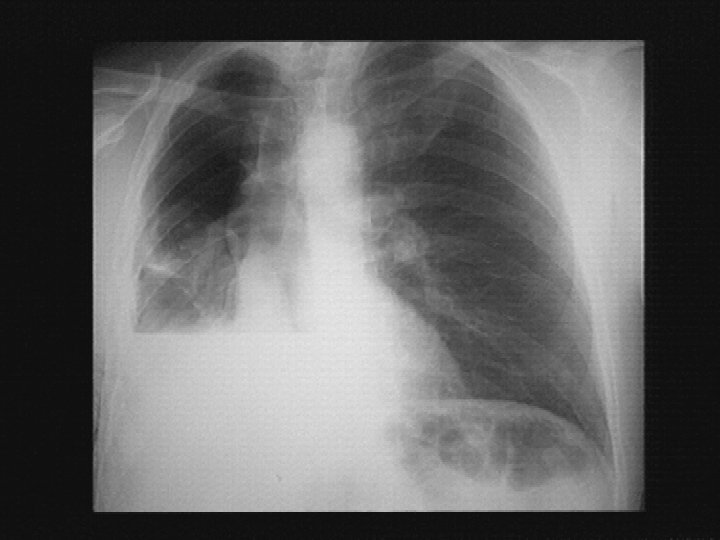

Cas particuliers « Poumon blanc unilatéral » • Déviation du médiastin? – Homolatéral au poumon malade: Atélectasie? – Controlatéral: épanchement? – Pas de déviation? : mixte, condensation?